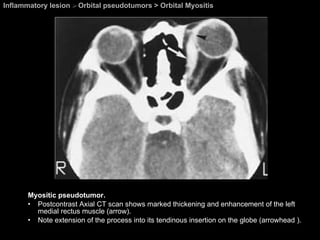

Orbital Myositis Orbital pseudotumors  One or more of the EOMs are infiltrated by an inflammatory process. Most frequently affected muscles =  superior complex and the medial rectus.

Orbital Myositis Orbital pseudotumors  CT findings Enlargement of the EOMs, which extends anteriorly to involve the tendon insertion. Obliteration of the fat between the periosteum of the orbital wall and the muscle cone.

Orbital Myositis Orbital pseudotumors  CT findings Enlargement of the EOMs, which extends anteriorly to involve the tendon insertion. Obliteration of the fat between the periosteum of the orbital wall and the muscle cone.   EOM enlargement Thyroid obthalmopathy . Pseudotumor . Carotidcavernous fistula . Granulomatous disease . Neoplasm  ( primary or metastatic

Inflammatory lesion  >  Orbital pseudotumors > Orbital Myositis Myositic pseudotumor.  Postcontrast Axial CT scan shows marked thickening and enhancement of the left medial rectus muscle (arrow).  Note extension of the process into its tendinous insertion on the globe (arrowhead ).